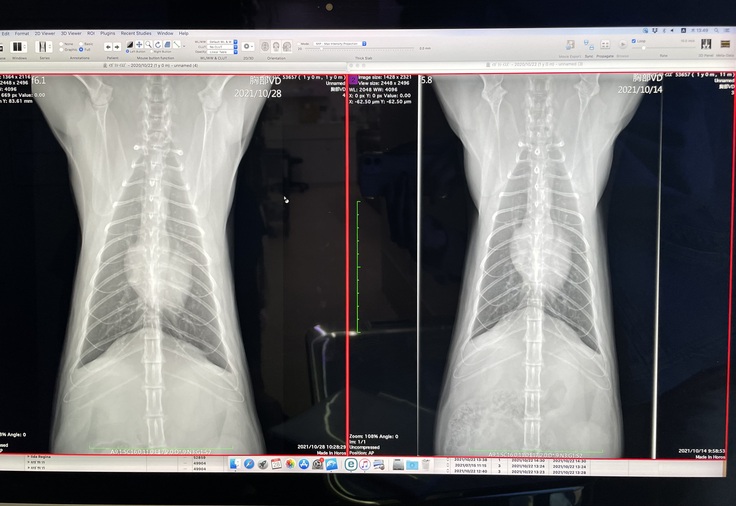

10/14と10/28のレントゲン。

最後に抗がん剤を打った10/7以降、腫瘍は今のところ大きくなるなどの変化はないのでホッとしています。